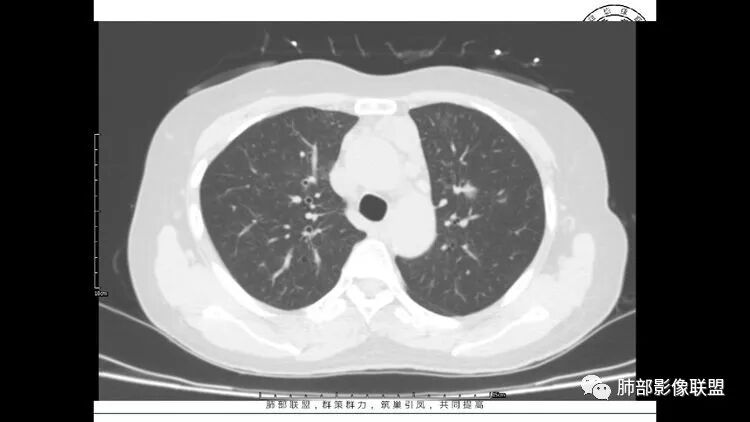

老年女性,长期使用激素史。双肺多发散在斑片状磨玻璃密度影及大小不等的薄壁含气囊腔,下肺相对较多较大。双肺多发结节,左肺上叶结节相对较大,界清,边缘光滑,分叶不明显。右肺下叶前外底段散在树丫。前上纵膈偏左侧不规则软组织团块,颗粒感,偏软。肺内囊腔及磨玻璃影考虑淋巴细胞间质性肺炎,或淋巴管肌瘤病。纵膈团块考虑淋巴管瘤。两者结合,考虑淋巴细胞增生病变。右肺下叶散在树丫,结核待排。双肺结节性质待定。

王秀仙

双肺多发散在斑片状磨玻璃密度影及大小不等的薄壁含气囊腔,下肺相对较多较大。双肺多发结节,界清,边缘光滑,分叶不明显。右肺下叶前外基底段散在斑片树芽。前上纵膈偏左侧不规则软组织团块,密度不均,其内可见不规则纤维样低密度,周围簇状小淋巴结。考虑1淋巴细胞间质性肺炎。2考虑纵膈胸腺淋巴瘤。

LIP影像重要线索一句话:

双肺下叶分布为主的间质改变(磨玻璃影、小叶间隔增厚)、散在气囊影(常有血管贴边)、边界不清小结节